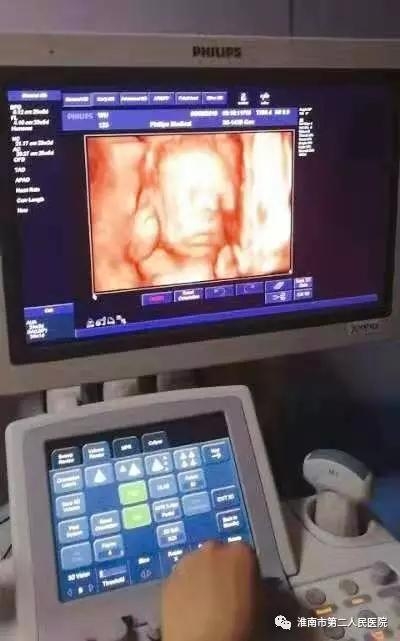

市二院四维彩超采用的先进飞利浦超声设备,能够多方位、多角度地观察宫内胎儿的生长发育情况,为早期诊断胎儿先天性体表畸形和先天性心脏疾病提供准确的科学依据,在优生优育方面起着非常重要的作用,是准妈妈们必不可少的检查项目。四维超声不存在射线、光波和电磁波等方面的辐射,对人体健康没有任何影响,能进行宫内写真,让准妈妈看到宫内宝宝的一举一动,亲身体会到宝宝的笑容相貌,为宝宝留下永久纪念。